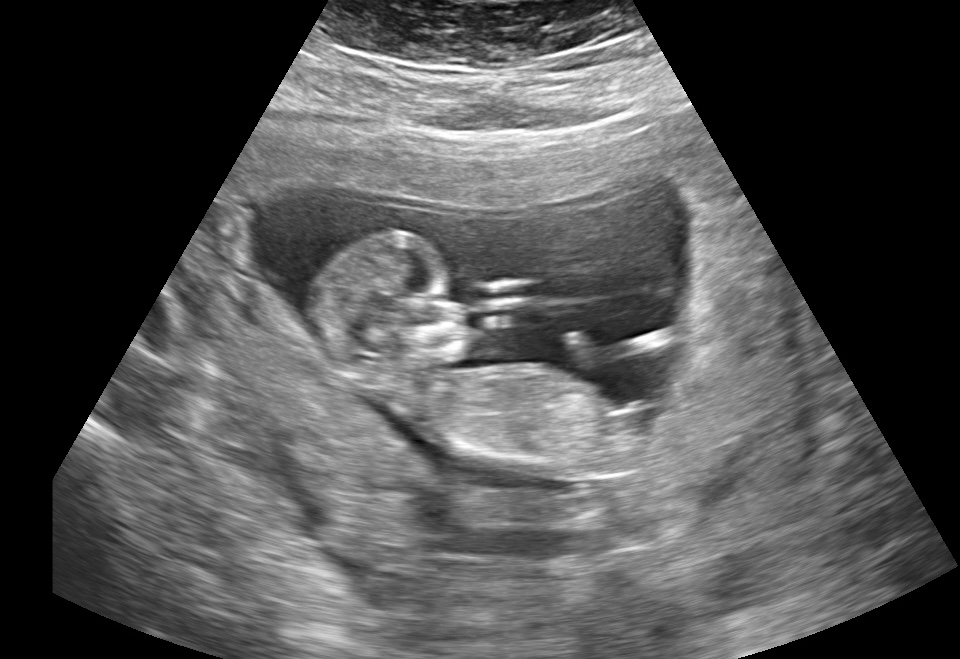

21 weken

Een echo na 21 weken.